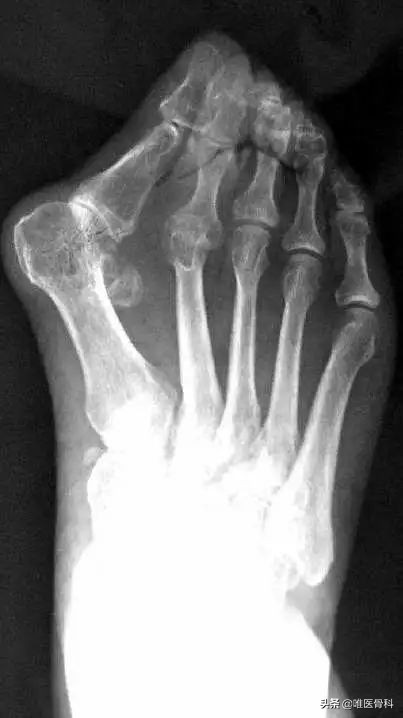

我们一般依据指外翻的程度还有患者的症状,将外翻大致分为4个阶段,如果您发现您的指已经越来越向外了,那就应该尝试对号入座,引起足够重视了。

大趾外翻20~40°左右,足趾重叠。正常人足底有两个向上的拱起,称为横弓和纵弓,这样走起路来比较有弹性,比较省力,而这个阶段的外翻患者,横弓因为足趾的挤压,基本已经消失、塌陷——形成我们所谓的“扁平足”。

大指外翻40°以上,指严重重叠,足趾在走路时基本上派不上什么用场,扁平足,十分疼痛,行走困难。